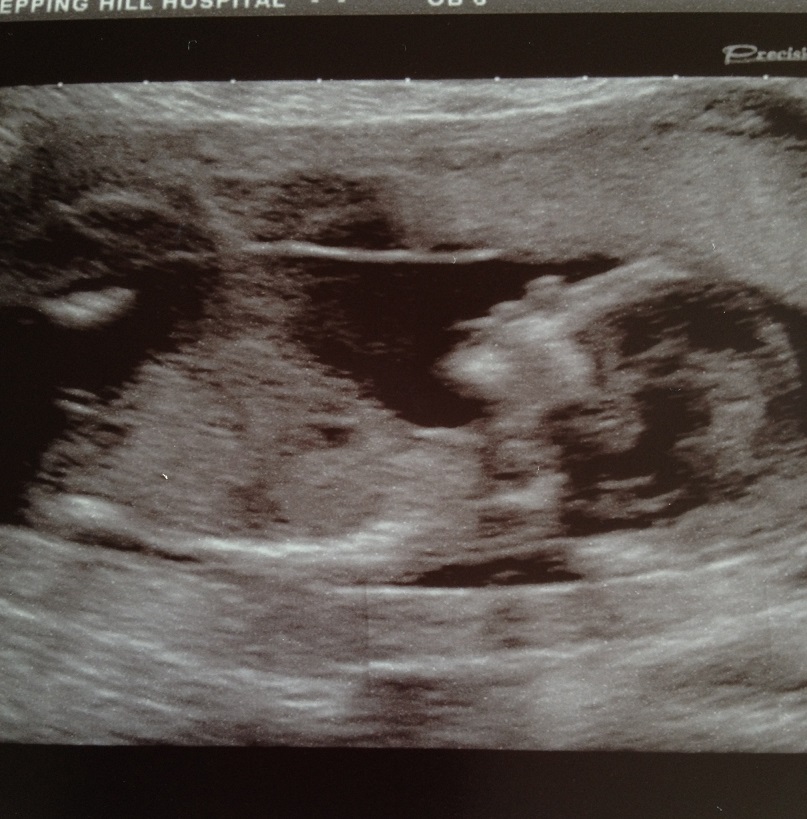

boy/girl any guesses? please x

Hi everyone, just had my 1st scan at 14 weeks 4 days. Just wondering if anyone had any ideas of whether boy or girl? im not sure whether the scan pics clear enough for the nub theory as personally i have no clue of how people guess this kind of thing lol. I thought itd be worth asking anyways, as this is my 2nd baby, the 1st i did the same post and between this site and another i had nearly 28 guesses, all saying boy, and you was all right :) thanks xx